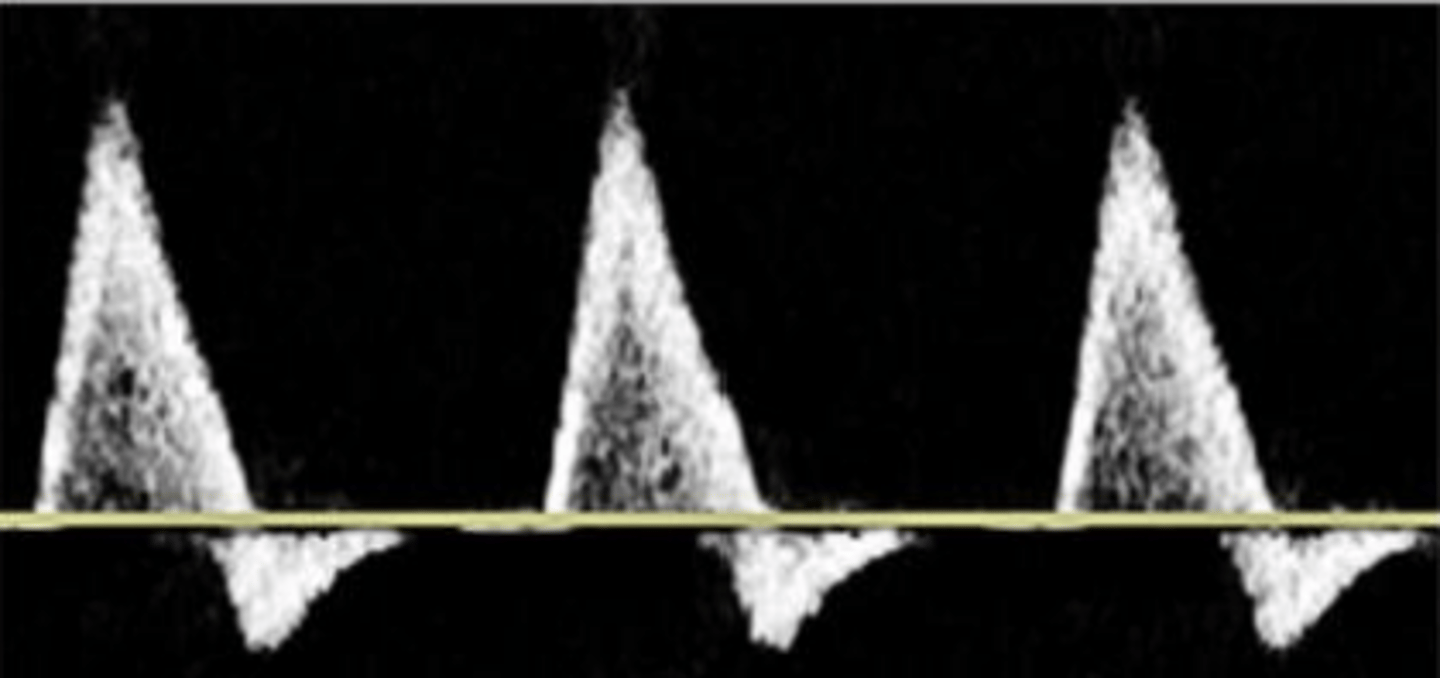

Low Resistance

broad downstroke and continual flow through out diastole